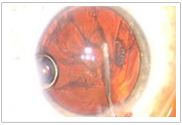

手術(shù)醫生可以在手術(shù)過(guò)程中監視全部眼前節

(1)高分辨率的視頻顯微鏡,實(shí)時(shí)成像

(2)一體化的、廣角的光學(xué)相干斷層

掃描(OCT),三維成像